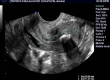

Figure 1

Aspect échographique montrant la ligne d’interface suivie jusqu’au fond où on note la présence d’une image hyperéchogène avec cône d’ombre postérieur (4,58mm)